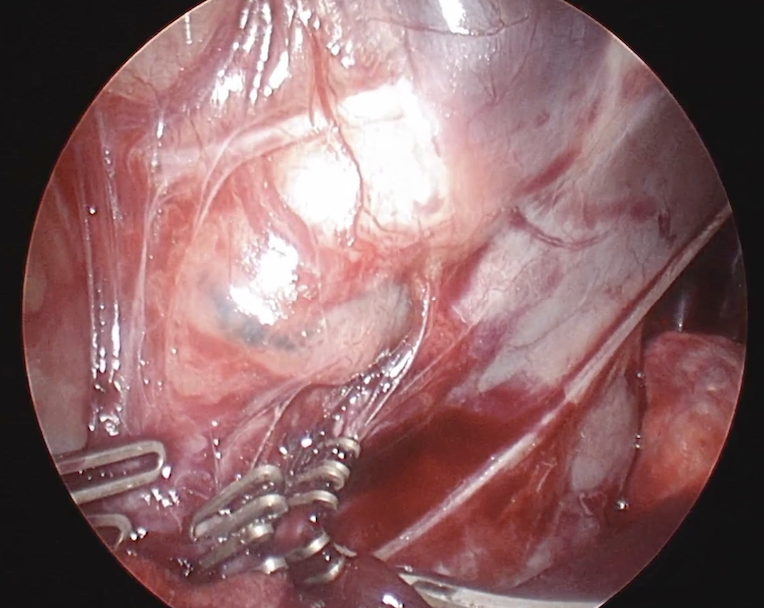

切除のために止血クリップを設置しているところ